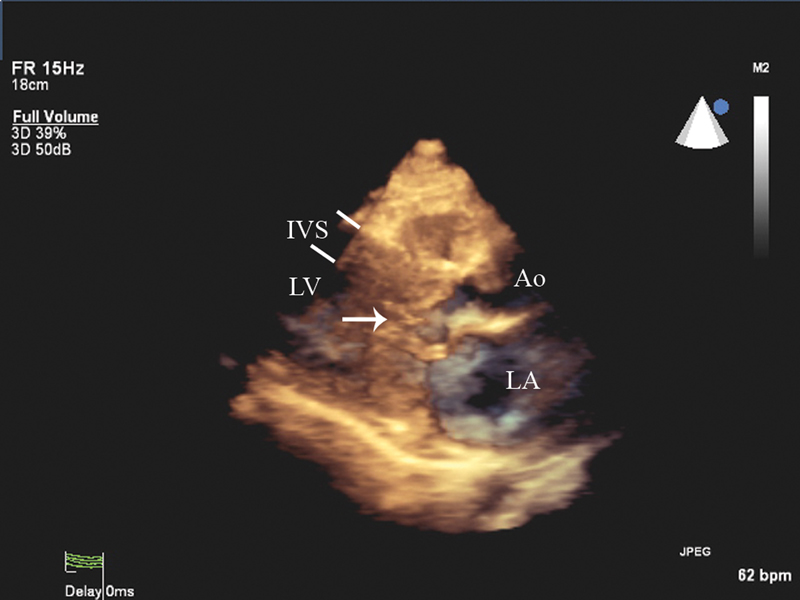

فحوصات تشخيصية لبعض امراض القلب والشرايين التاجية